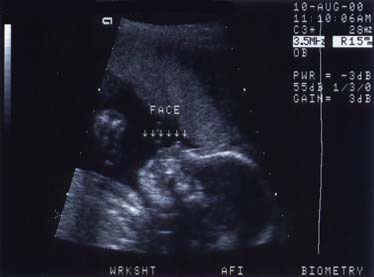

8/10/2000